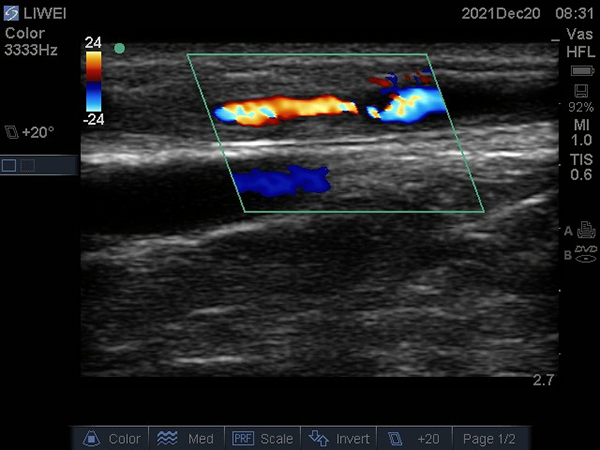

患者李某,男,51歲,規(guī)律血液透析,5年前在徐醫(yī)附院行自體動靜脈內(nèi)瘺(AVF)。近期AVF震顫減弱,流量欠佳,只能達到200ml/min,遂到徐醫(yī)附院就診。術(shù)前超聲檢查示AVF動脈穿刺點上游血管狹窄,長度約4cm,最狹窄處僅有2.5mm,伴吻合口狹窄;颊呓(jīng)過PTA治療,AVF震顫明顯增強,流量達到1793ml/min,完全滿足透析要求,手術(shù)成功。